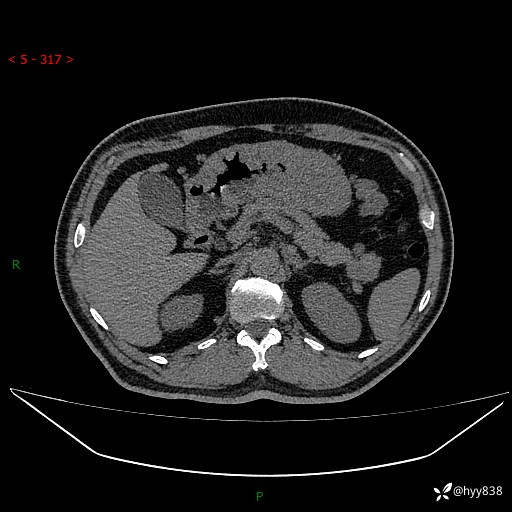

静脉期